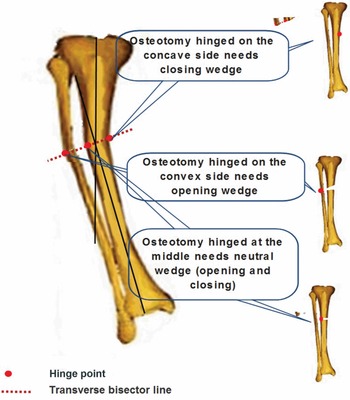

Principles of Deformity Correction: Including the Complete。mqdefault.jpg。Principles of deformity correction | PPT。茨城県産コシヒカリ こだわり新米 5kg 令和6年9月収穫。。。タイトル principles of deformity correction著者 Dror Paley やや経年変化はございますが、書き込みや破れ等はございません。Principles of deformity correction | PPT